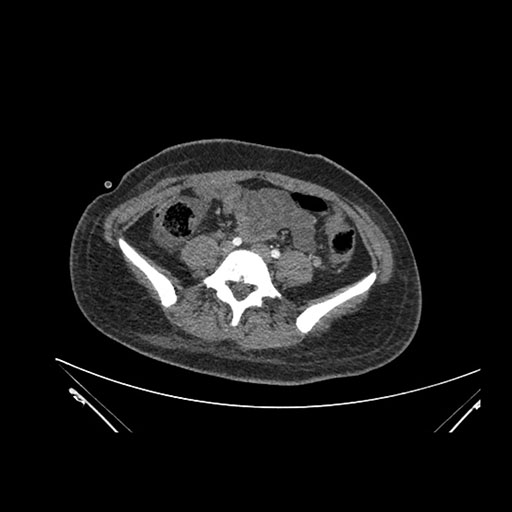

Imaging Analysis

Look through the patient's CT scan to identify any areas of concern for the necessary procedure.

Based on initial findings, which issue(s) would you be most concerned about?